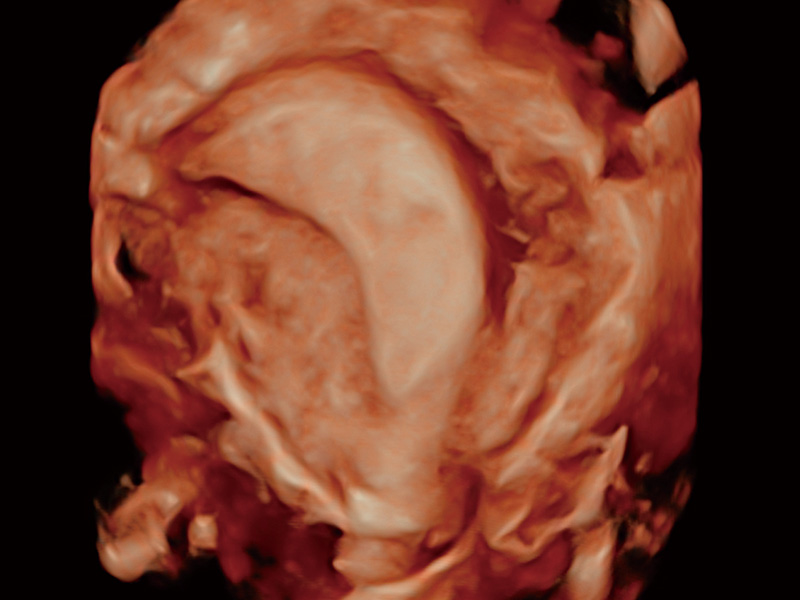

“生育问题”即关系民族复兴,也关系亿万家庭的幸福。随着婚育年龄推迟、社会压力增加等因素,越来越多人群也面临着“生不出、生不好”的问题。辅助生殖作为治疗不孕不育最有效的方法之一,也逐渐成为育儿新希望。而超声检查能为生殖需求人群的初诊评估提供宝贵的信息。 P20 Elite是哈哈体育官网匠心打造的一款生殖应用型彩超。她继承哈哈体育官网高端极光平台,突破性地将多款新型芯片及硬件模块进行整合,均衡了高端系统性能与小巧灵动机身。P20 Elite卓越的图像质量搭载专科探头,旨在为您提供全面的辅助生殖解决方案。

P20 Elite配备了丰富的生殖探头群和临床应用功能,在卵泡监测、穿刺取卵、胚胎移植、妊娠确认等领域,为生殖需求人群提供了新的临床机会,重新定义高端超声如何应用于生殖健康检查。